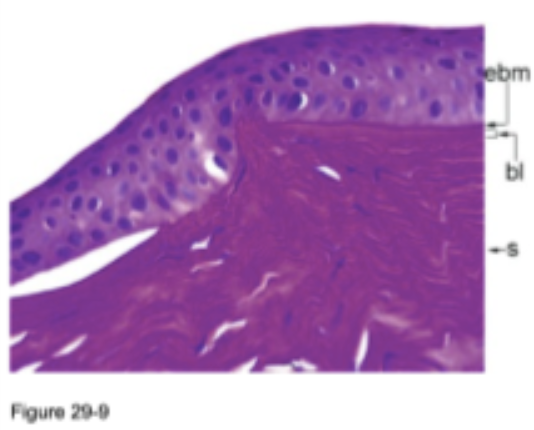

keratoconus